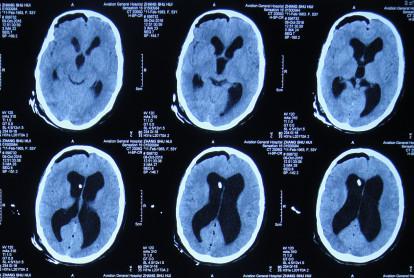

第2次出院后4月余即2016年6月7日,因第3次“发热”就诊当地某医院中医门诊,经中医治疗近两月时间。于2016年6月21日复查头颅CT:幕上脑室仍扩张(图-7)。治疗期间发热曾缓解,但之后发热仍反复。

图-7:2016年6月21日头颅CT

住院后3天即2016年8月19日,查头颅CT:幕上脑室扩张(图-9)。

图-9:2016年8月19日头颅CT

第3次出院后21天即2016年9月23日,复查头颅CT:幕上脑室仍扩张(图-10)。

图-10:2016年9月23日头颅CT